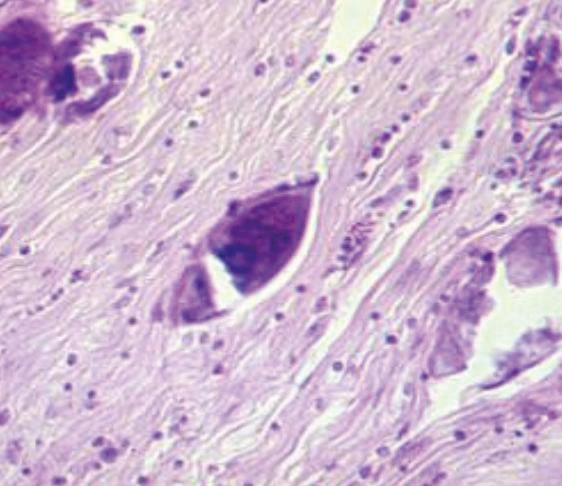

Рис. 15. Яйца кровяной шистосомы (фото биопсии мочевого пузыря)